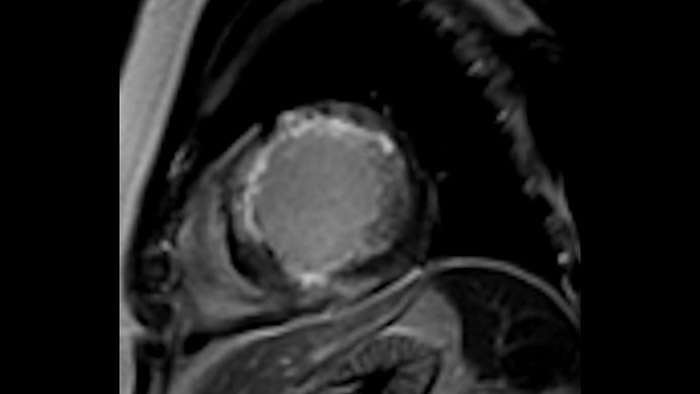

MyoStrain

Transforming the Cardiac Care Continuum

Today's diagnostics often cannot detect heart dysfunction until symptoms occur. MyoStrain utilises segmental strain to measure 48 segments of the heart and provides physicians with a unique diagnostic tool to help identify regional dysfunction before the heart as a whole is affected.